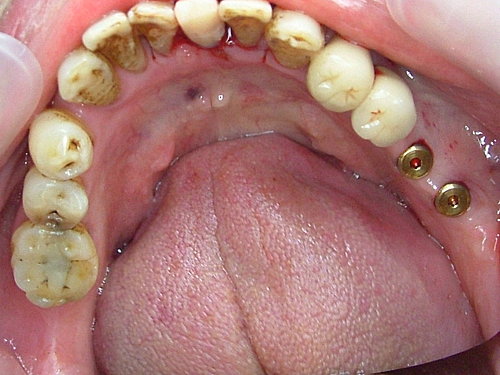

植牙手術後三個月 .... 癒合良好 .... 但牙齒刷不乾淨 牙結石多 ...

裝上假牙 大功告成 .... 拜託 !牙齒還是沒刷 看到一層厚厚的牙結石 .... 總不能天天來診所洗牙吧!